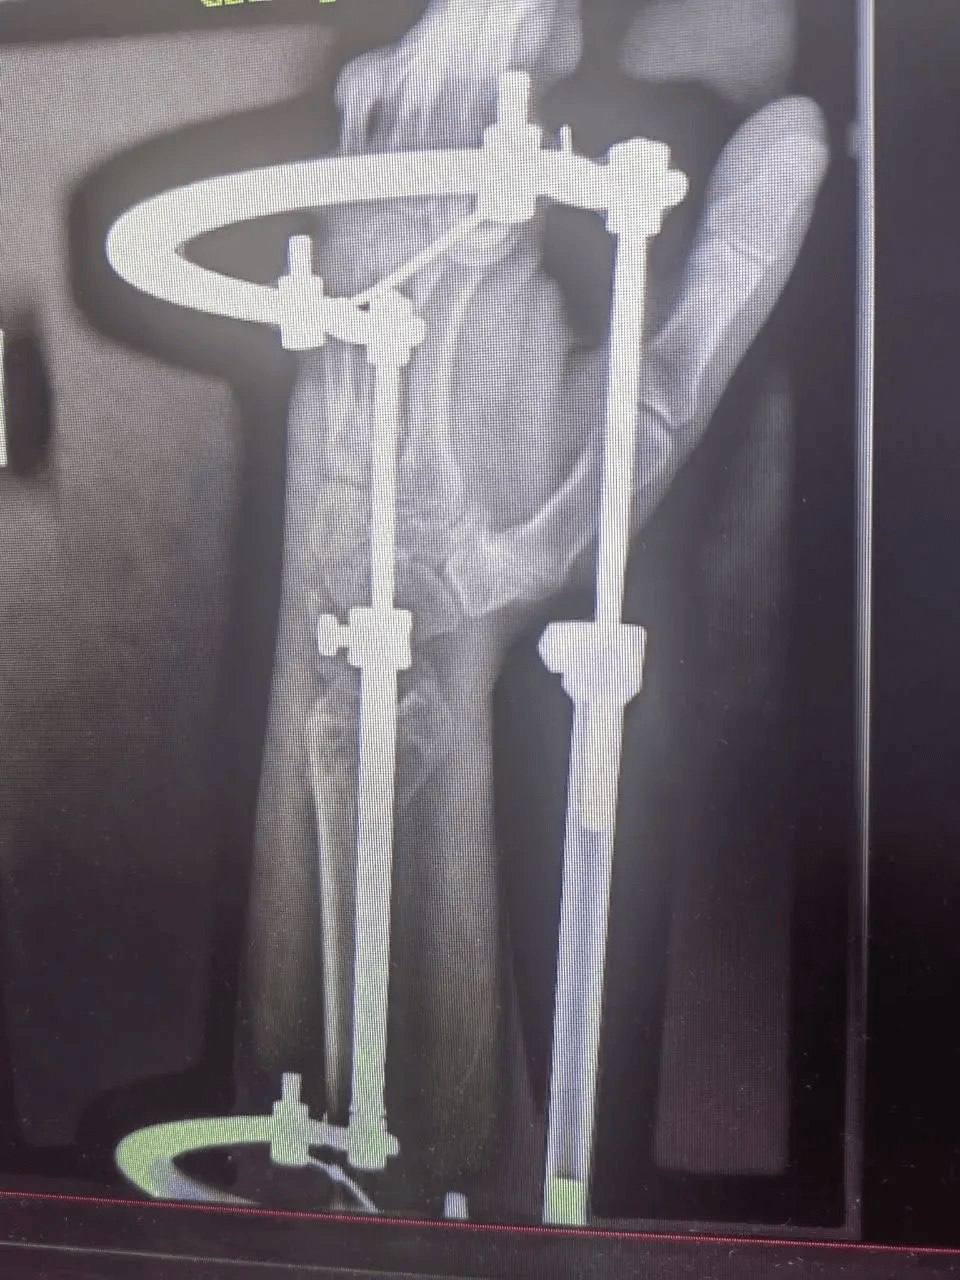

В больницу скорой помощи поступил 52-летний мужчина с тяжёлой политравмой после падения. У него были множественные переломы и повреждения, требующие комплексного лечения.

К работе подключилась команда специалистов: челюстно-лицевые хирурги, травматологи, нейрохирурги и неврологи провели операции и терапию. Несмотря на осложнение в виде токсического гепатита, врачам удалось стабилизировать состояние пациента.